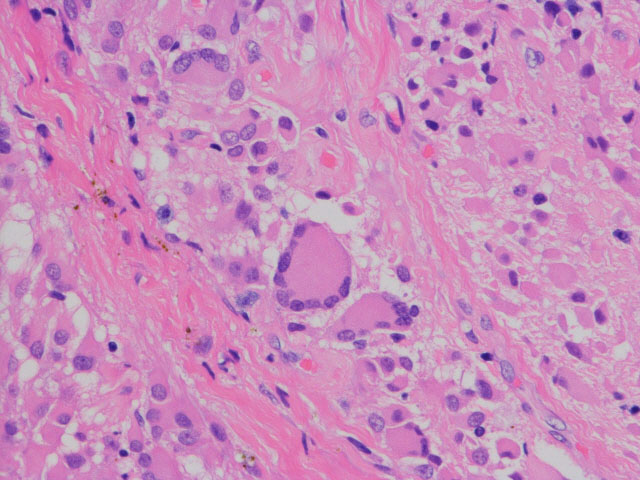

- 病理像では,好酸性の胞体 glassy eosinophilic cytoplasm を有する不整形の巨細胞の存在が特徴です

- 核は,多型で複数核 pleomorohic binucleate to multinucleate,クロマチンは粗,核小体が明瞭で神経節細胞様の大型のものもみられます

- 腫瘍細胞にはGFAP, vimentine, S-100が陽性で,巨細胞はNF, NSEなどが陽性となることがあります

- 血管増殖像はなく,核分裂もなく,組織の異型性に反して臨床的には良性腫瘍の性格を呈します

SEGAの病理像

基本的には,大きくて太った細胞 large plump cells で構成されます。gemistocytic astrocytesにています。

polygonal cells, ganglionic-like cells with a clear nucleoli, and plump large tumor cells resembling gemistocytic astrocytes

multinucleated giant cells

perivascular pseudorosettes, sweeping fascicles